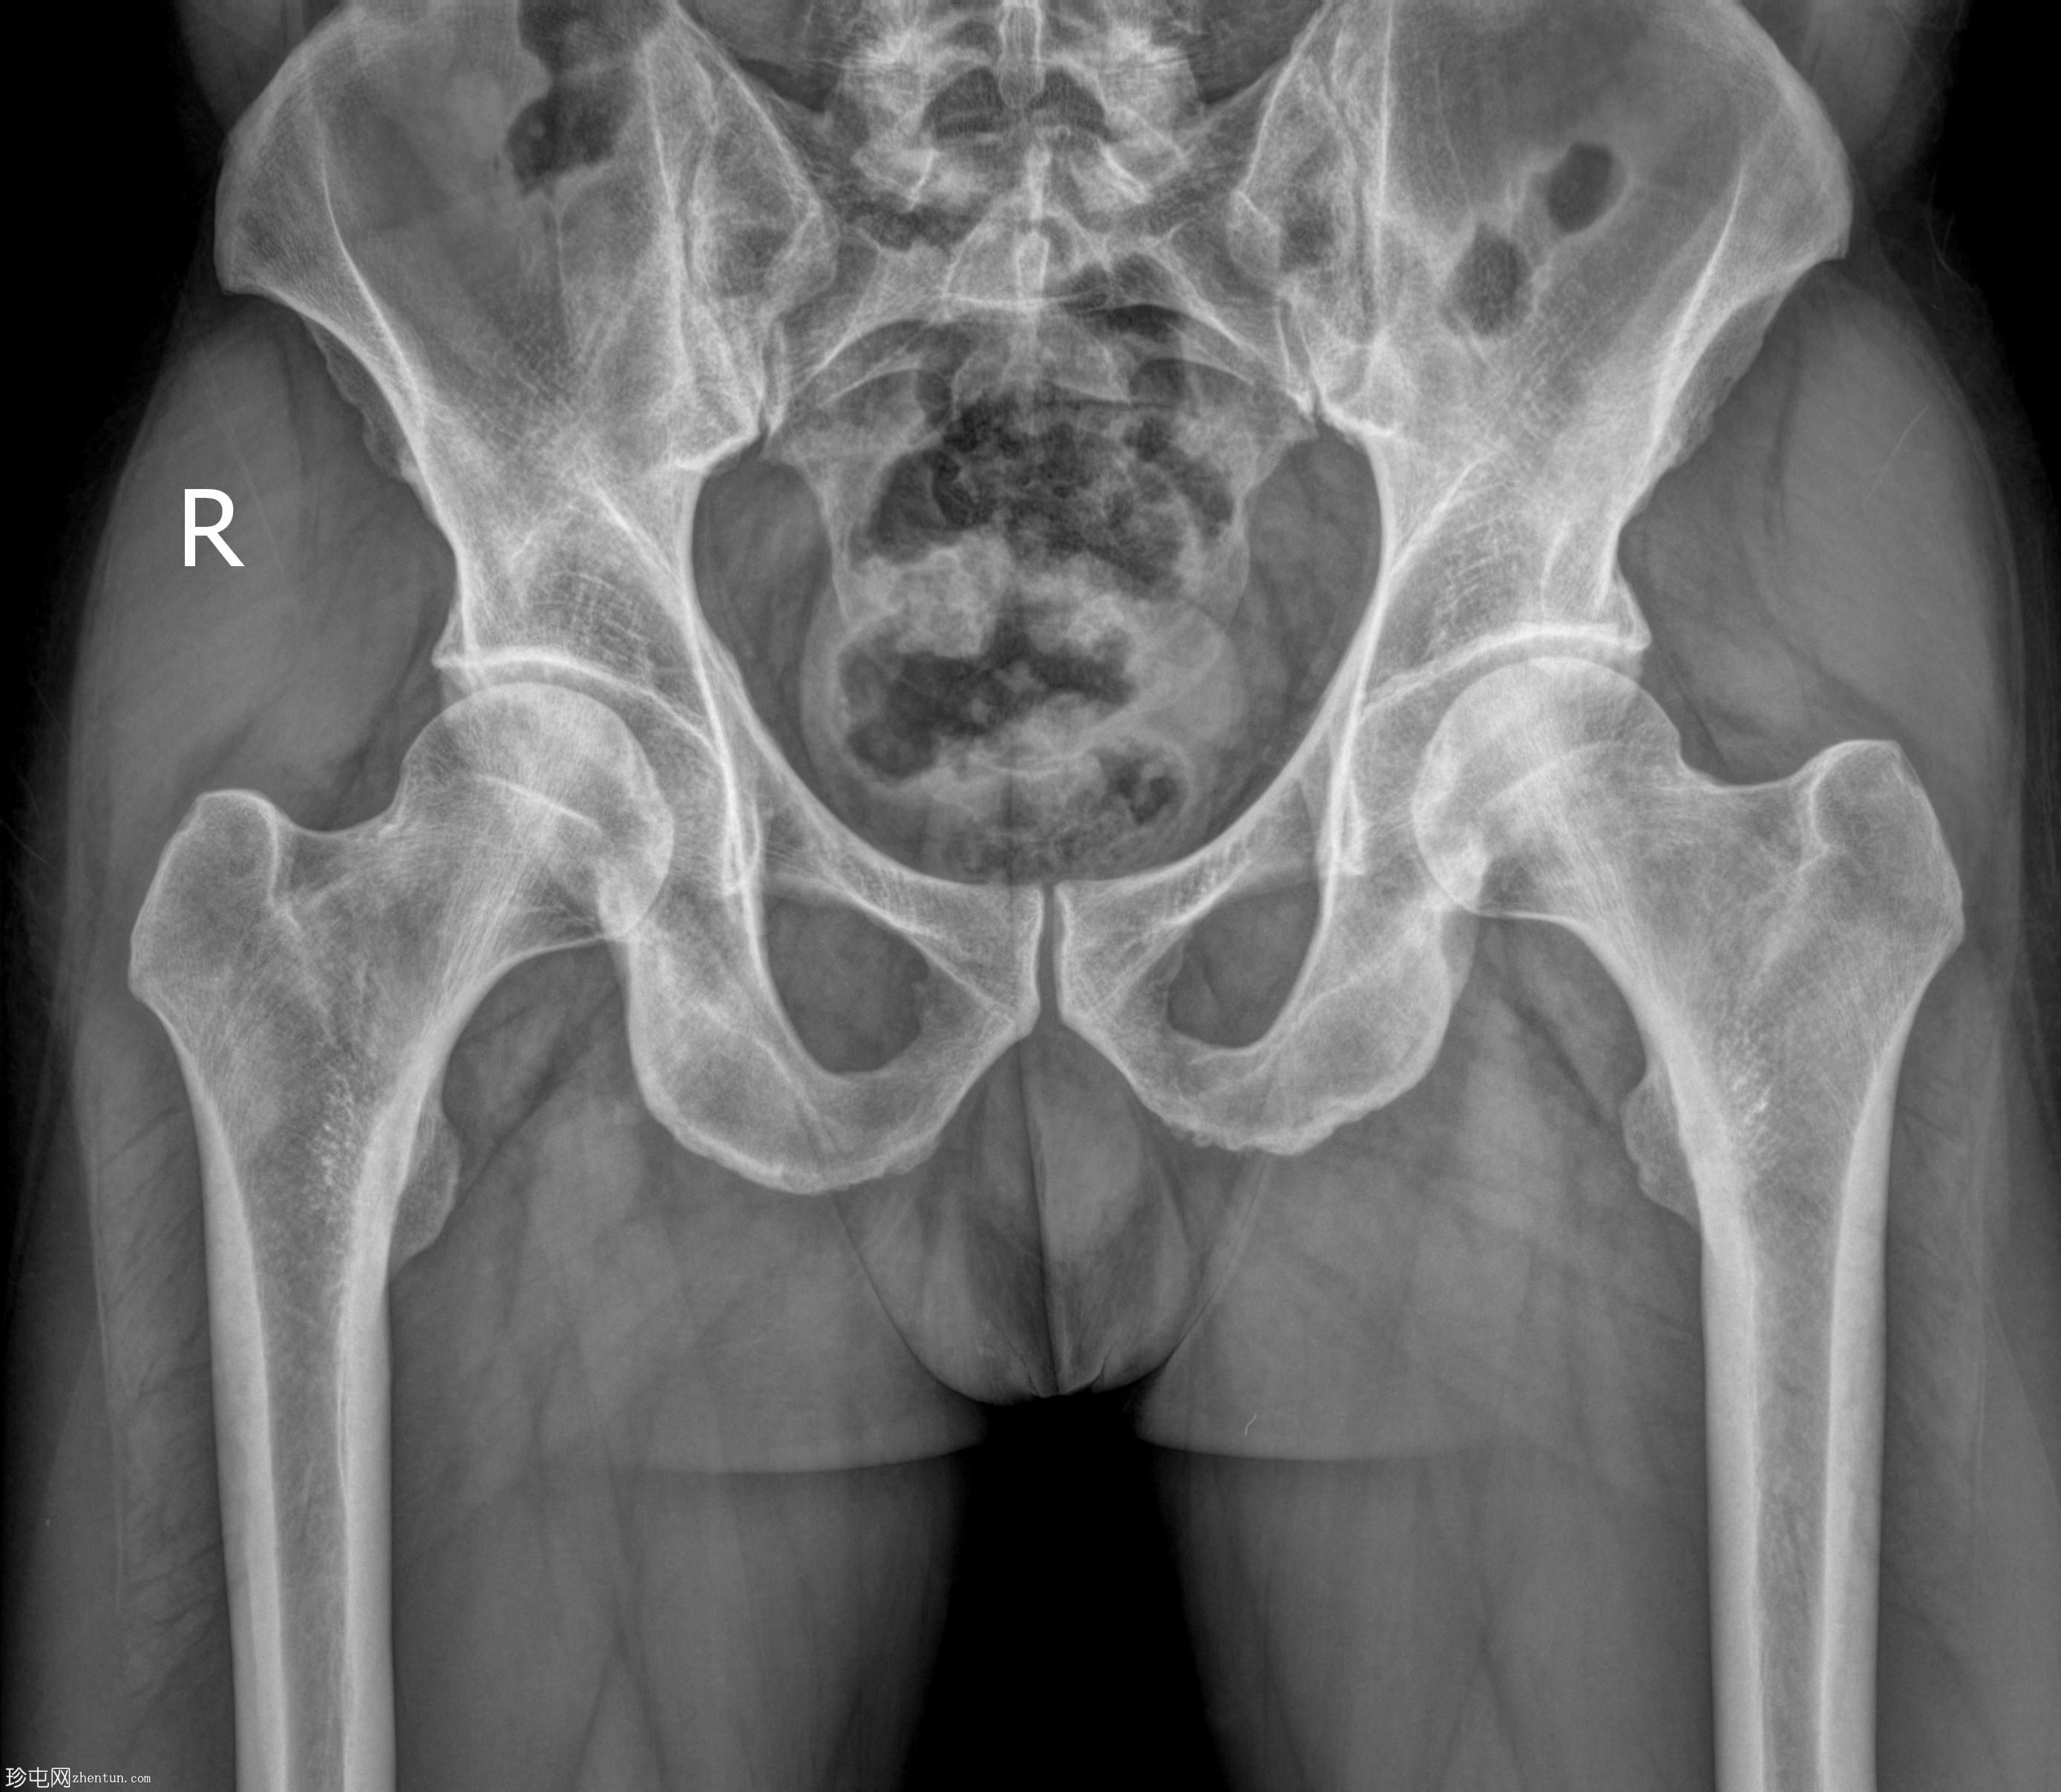

正位

经脓性分泌物开口注入造影剂,显示右侧肛周脓肿显影。

未见造影剂明显外渗至肛管或直肠。

透视瘘管造影图像显示右侧肛周脓肿较大,与肛管或直肠无交通。